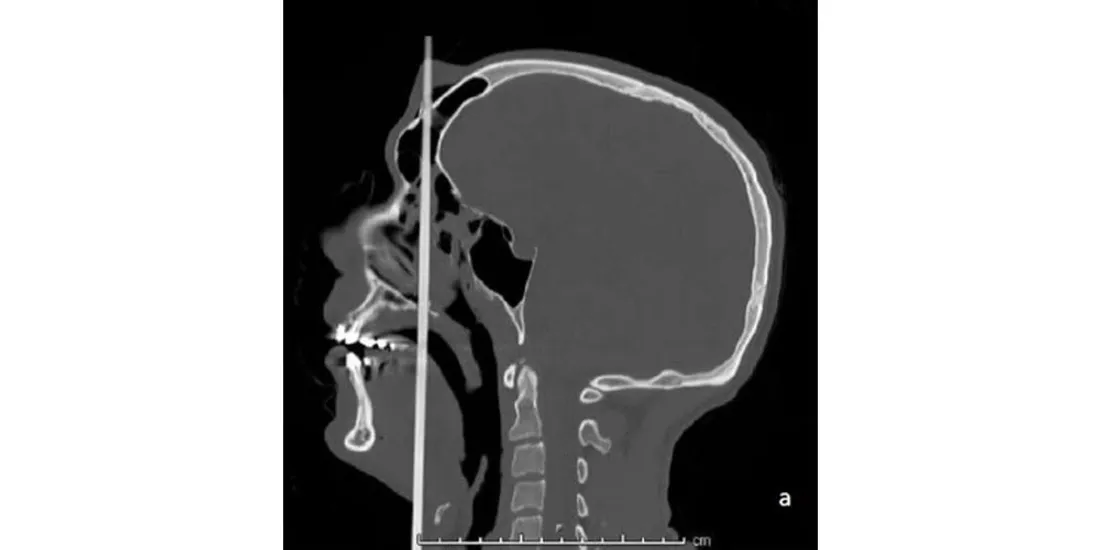

C'est un cas clinique exceptionnel qu’il a été donné d’observer à des chirurgiens et réanimateurs du CHU de Reims fin janvier. Après une rupture amoureuse, un Rémois de 28 ans a souhaité mettre fin à ses jours avec une arbalète, en se tirant une flèche dans la tête. Tirée depuis la base du cou et ressortie par le front, elle n’a, par miracle, provoqué aucune lésion vasculaire, cérébrale ou nerveuse, comme le raconte un blog médical hébergé par nos confrères du Monde.

La flèche a épargné toutes les structures vitales

Transféré à l’hôpital, le jeune homme a été soumis à un scanner, qui a révélé l’absence de lésion de quelque nature que ce soit (vasculaire, cérébrale et nerveuse). "La flèche a traversé le plan de la ligne médiane de la face tout en épargnant cependant toutes les structures vitales de la tête et du cou", décrit l’article, qui reprend une publication scientifique (European Annals of Otorhinolaryngology) parue le 22 janvier dernier.

Placé sous sédatif et alimenté en oxygène, le patient s’est fait retirer la flèche avant d’être intubé. Aucune lésion n’a non plus été constatée dans la bouche. Après 48h en soins intensifs et un passage dans le service d’ORL, il a été envoyé en psychiatrie.